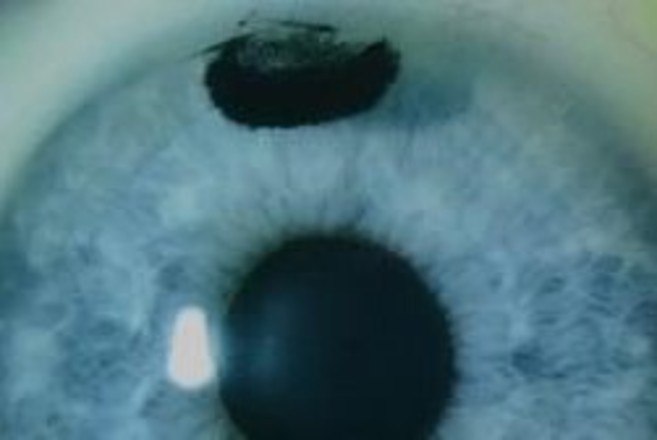

"Nós utilizamos um bisturi para criar um pequeno bolso no centro da córnea, exatamente no local onde ela fez a cirurgia. Depois disso nós colocamos uma camada de tinta e fechamos o bolso", contou o Dr. Saldanha

"O mais bonito sobre isso é que ela gostou tanto do teste que pediu para que tatuássemos a área poucas horas depois, nos dois olhos", disse o médico